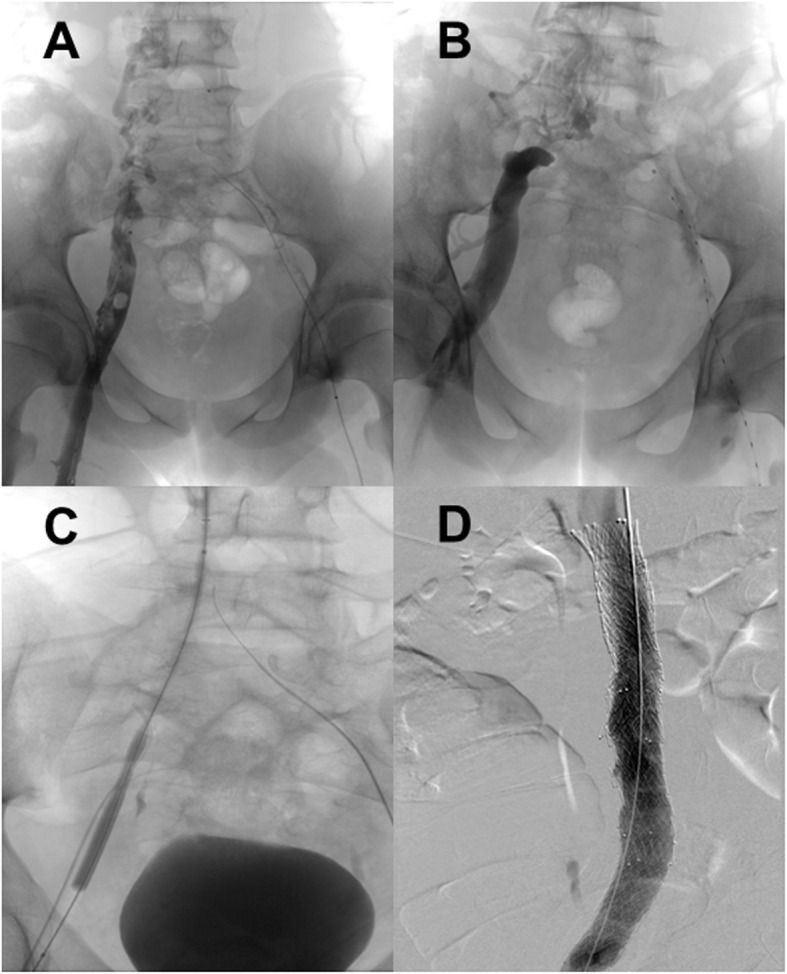

Fig. 1.

Angiography images in our 14-year-old patient. A Angiography shows a thrombotic right pelvic axis with suspected inferior vena cava atresia and prominent paravertebral collaterals; B Angiography confirms inferior vena cava atresia; C Location of the occluded inferior vena cava by rendezvous-technique between superior and inferior vena cava; D Recanalized inferior vena cava after successful stenting

Recanalization of the right lower extremity and pelvic axis was subsequently achieved, whereby IVC occlusion was confirmed (Fig. 1B). However, the left pelvic vessels remained thrombotic even after 5 days of catheter-directed thrombolysis.

Surprisingly, one of the angiographies allowed for location of the occluded area of the IVC by rendezvous-technique between the superior and inferior vena cava, which prior to this had been thought to be atretic (Fig. 1C). The vessel was successfully recanalized using balloon dilation and subsequent stenting (Fig. 1D).